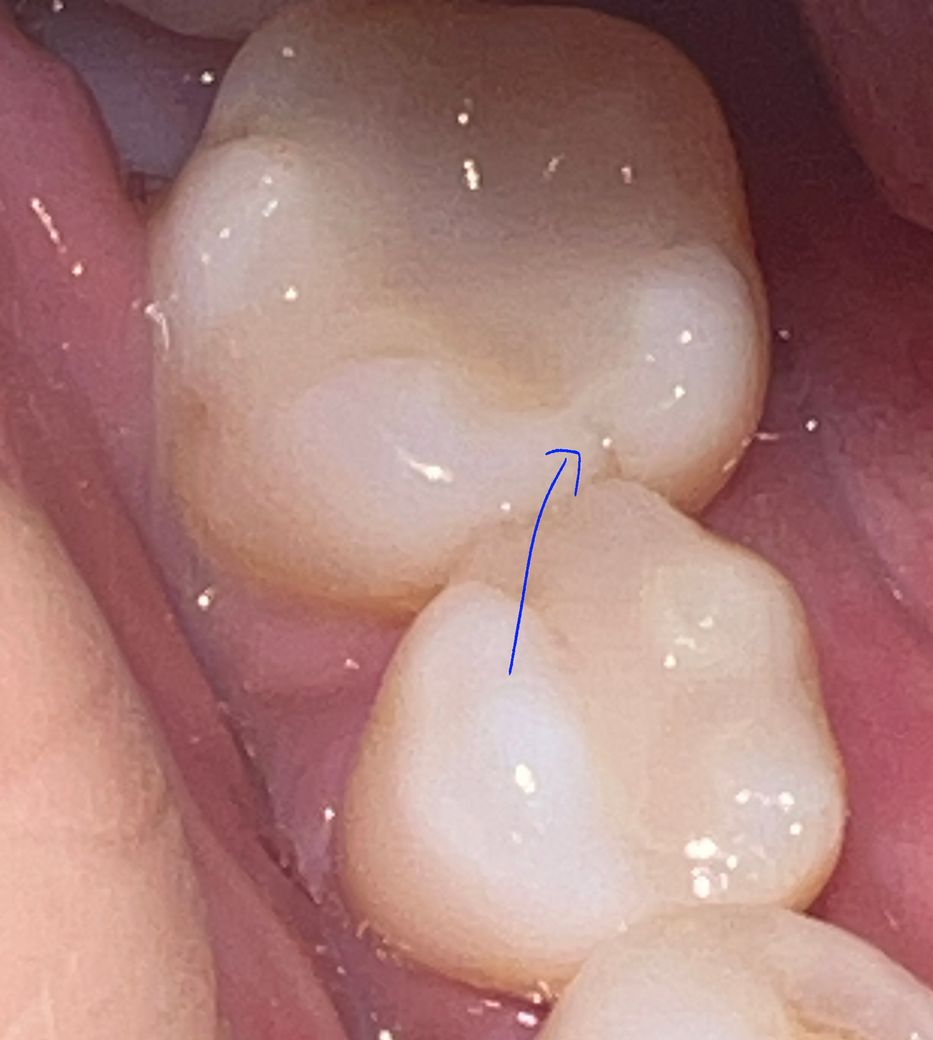

씹을 때 찌릿한 통증이 있어 큐레이로 검사해봤는데요.

큐레이상에선 붉은색 부분이 없는데 화살표 친 부분 금간거로 보이네요.

금간 거 아닌가요? 실금도 아닌 진한 금같아 보이는데요.

나중에 통증이 사라져도 크라운 안씌우고 그냥 인레이로 놔둬도 되나요?

계속 쓰다가 뿌리끝까지 금이 진행할수도 있지 않나요?